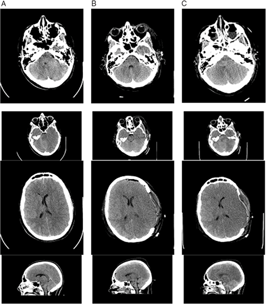

Brain and cervical spine CT scanning within 1 hour of presentation showed no fractures of the skull or cervical spine (Figure 1). There was significant, generalized cerebral edema, worse on the left with 3 mm midline shift to the right. There was a thin left subdural hematoma (SDH) about 2 mm in width over the convexity of the left cerebral hemisphere (Figure 1, column A). Mannitol was administered (∼1g/kg), and surgical decompression began 2.5 hours after presentation. A large, left decompressive craniectomy (9 × 14 cm) was performed, the SDH evacuated, and a parenchymal intracranial pressure (ICP) probe was placed. Mannitol was administered once intraoperatively, with no clear response. Initial post-op ICP was normal (5–8 mmHg), and the brain CT showed persistent edema with resolution of the midline shift and confirmed complete SDH removal (Figures 1 and 2, column B). Initial postoperative serum sodium was 149 mmol/L and peaked at 154 mmol/L 9 hours post-op. Urine output was normal, as per institutional Diabetes Insipidus (DI) protocol.

Figure 1: Non-contrast brain CT 2 hours after the patient’s injury (column A), 2 days post-injury (column B), and 3 days post-injury (column C). (A) There is generalized cerebral edema, moreso on the left side, with effacement of the sulci, uncal herniation, 3 mm midline shift to the right, and a small left-sided SDH approximately 2–3 mm thick (arrows). (B) Two days after left decompressive craniectomy with persistent generalized cerebral edema and interval resolution of the midline shift and signs of uncal herniation, and drainage of the SDH. (C) Progression of cerebral edema with complete absence of gray–white matter differentiation.

Figure 2: Additional Images of non-contrast CT head imaging 2 hours after the patient’s injury (column A), 2 days post-injury (column B), and 3 days post-injury (column C). There is initial generalized cerebral edema with early midline shift and a small left-sided SDH. The progression of cerebral edema and loss of gray–white matter differentiation, despite surgical and medical intervention including craniectomy, can be seen.

The first post-operative day, the patient remained unresponsive with ICP of 11–12 mmHg. The second day ICP was 12–14 mmHg, and DI developed (serum osmolality 320 mmol/kgH20 and urine osmolality 141 mmol/kgH20), and was stabilized by vasopressin infusion. The third day, ICP gradually rose to 30–35 mmHg and then spiked to 50 mmHg. The left pupil became fixed and dilated despite aggressive ICP management including four doses of hypertonic saline (3 mL/kg each), adequate pain control, muscle paralysis, normal BP and temperature maintenance, targeted low-normal pCO2 through careful ventilator management, and close monitoring of fluid balance. The brain CT showed worsening cerebral edema with compression of the ventricles, effacement of the cisterns, and suspected brainstem hemorrhage (Figures 1 and 2, column C). Three days post-op, the only brainstem reflexes were cough and spontaneous breathing, and the following day, gag and spontaneous respiration were absent.